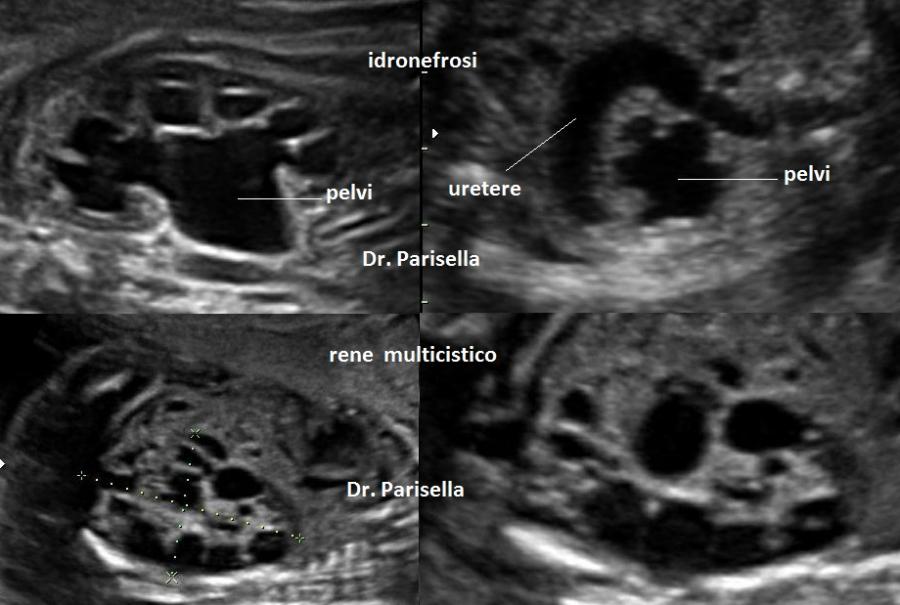

Possono essere presenti: idrope, cardioaptie congenite, labiopalatoschisi, oligoamnios, anomalie genito-urinarie, anomalie gastro-intestinali, anomalie del SNC.

Sono frequenti le Anomalie renali e i femori mostrano degli speroni marginali. Le metafisi sono irregolari.     La polidattilia è postassiale.

Sono presenti labiopalatoschisi, anomalie genitourinarie ed anomalie gastrointestinali. Può essere presente idrope ed ascite.